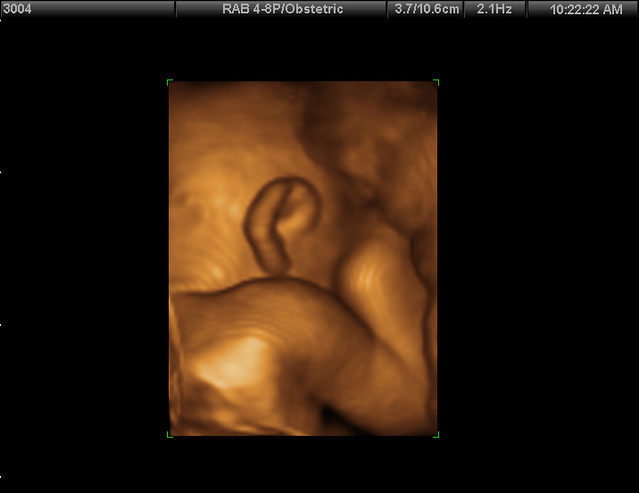

Los Ultrasonidos 4D son una evolución de los tradicionales ultrasonidos 2D y 3D. En lugar de producir imágenes planas en blanco y negro, los Ultrasonidos 4D producen imágenes en 3D con movimiento en tiempo real. Esto significa que las madres y sus familiares pueden ver a su bebé moverse, sonreír y hacer muecas dentro del vientre.

Desde un punto de vista médico, los Ultrasonidos 4D también son muy útiles. Los profesionales médicos pueden monitorear el desarrollo y la salud del bebé con mayor precisión y detalle. Además, estos ultrasonidos pueden ayudar a identificar posibles problemas de salud en el bebé a tiempo, lo que permite a los médicos tomar medidas para corregirlos antes de que sea demasiado tarde.

Otro aspecto positivo de los Ultrasonidos 4D es que ayudan a las madres y sus familiares a formar un vínculo emocional más fuerte con el bebé antes de su nacimiento. Ver a su hijo moverse y sonreír les brinda una idea más clara de quién es su bebé y les permite conectarse emocionalmente con él o ella antes de su nacimiento.